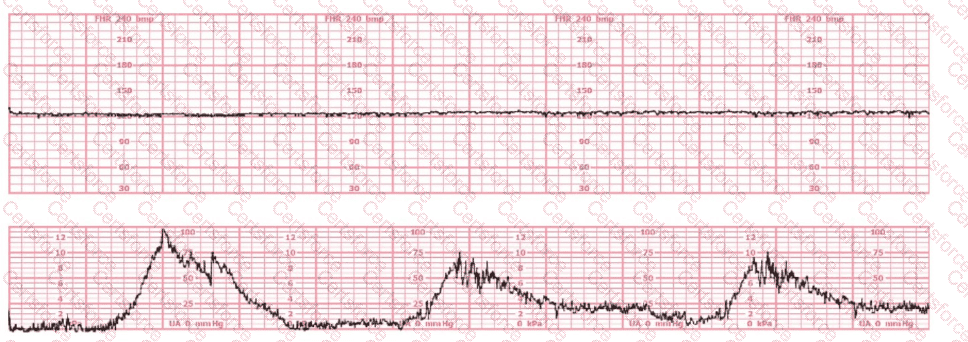

The tracing shown is from a woman at 28-weeks gestation in the post-anesthesia care unit (PACU) after an appendectomy. She is alert and awake. Based on this fetal heart rate pattern, the most appropriate intervention is: